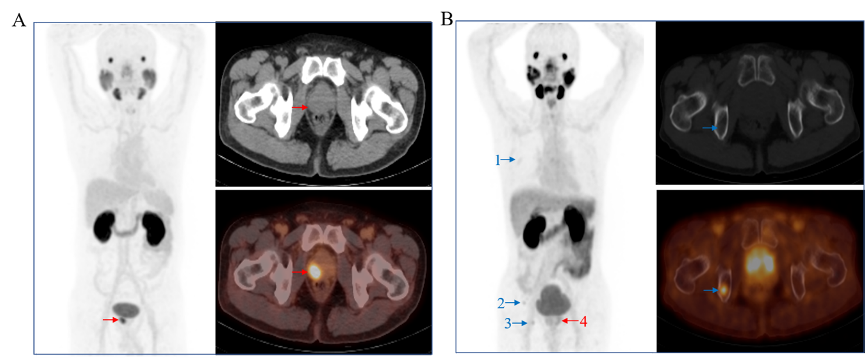

杨志的主要研究领域是生物医药中的放射性药物领域,他“立足临床,服务临床”,进行新型放射性药物的研发及临床转化,在药物研发过程中充分考虑药物的成药性和可商业化,为新型探针的成果转化奠定基础,有效推动核医学逐渐从肿瘤治疗的“幕后”步入“台前”。目前他已开发肿瘤诊疗药物二十余种,实现成果转化4项,合同转让金额近6300万元。将CD20抗体(美罗华)进行99mTc标记,已成功应用于寻找乳腺癌、黑色素瘤、骨与软组织肿瘤等的前哨淋巴结。创新性地开发了集传统18F和68Ga标记探针优势为一体的Al18F-PSMA-BCH,临床试验有效证实了该类探针的稳定性和有效性,该探针已进行临床试验4500余例,已获得国家药品监督管理局核准签发的《药物临床试验批准通知书》,并成功豁免Ⅱ期临床试验,目前正在开展Ⅲ期临床试验。针对该靶点,和北京大学第一医院杨兴教授团队合作,通过改变探针的结合核心基团,获得了PSMA-P137系列探针,可降低膀胱的放射性摄取,有望用于前列腺癌的精准诊疗。过氧化氢酶标记上β治疗核素177Lu并与海藻酸钠混合得到177Lu-Cat(ALG),可用于实体肿瘤的局部放射性内照射治疗。

Al18F-PSMA-BCH PET/CT 为前列腺癌的精准诊断提供基础

177Lu-Cat(ALG) 用于骨与软组织肿瘤的内照射治疗